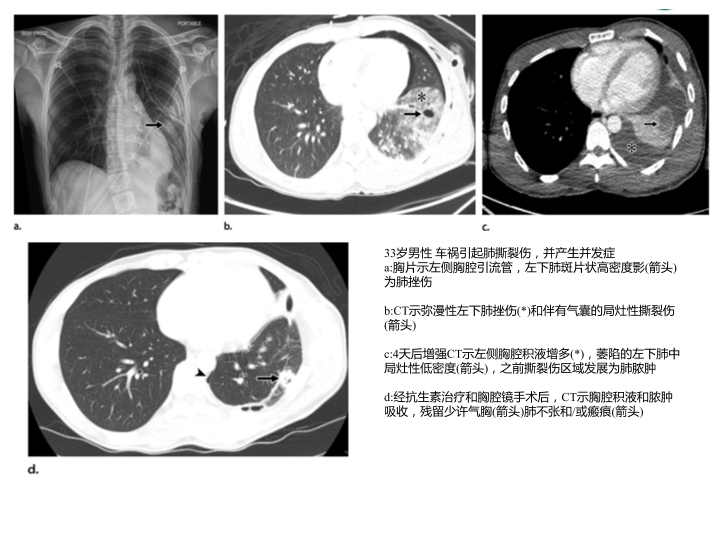

胸部外伤及胸腔积液处理